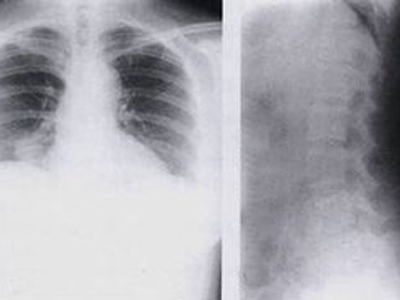

骨膜反应图 (9)

骨膜反应图 (8)

骨膜反应图 (7)

骨膜反应图 (6)

骨膜反应图 (5)